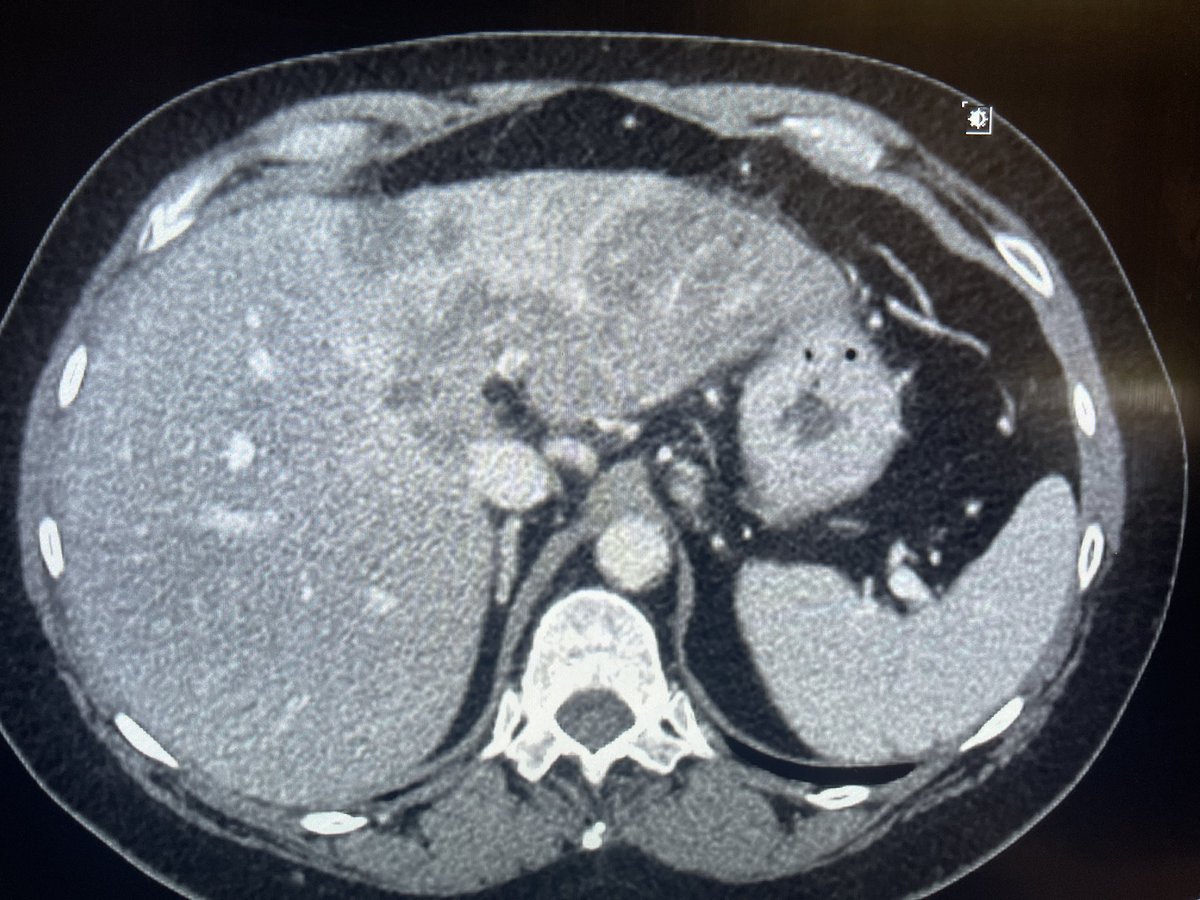

New study @AnnalsofIM bit.ly/2Km3KYu by @DrTalenfeld @WeillCornell: Percutaneous ablation for T1a #renalcancer has similar 5-year survival rates to radical nephrectomy but with far fewer 30-day complications and less #kidneyfailure.